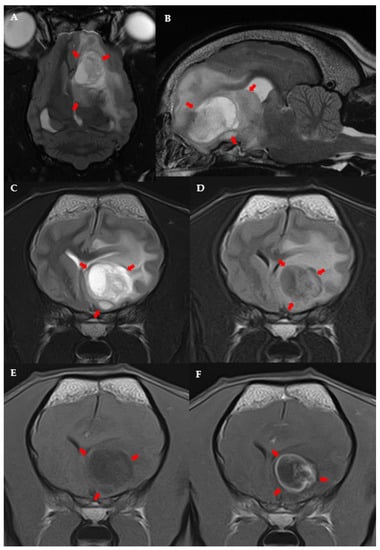

3.3. MRI Features and Localisation of Suspected Glioma